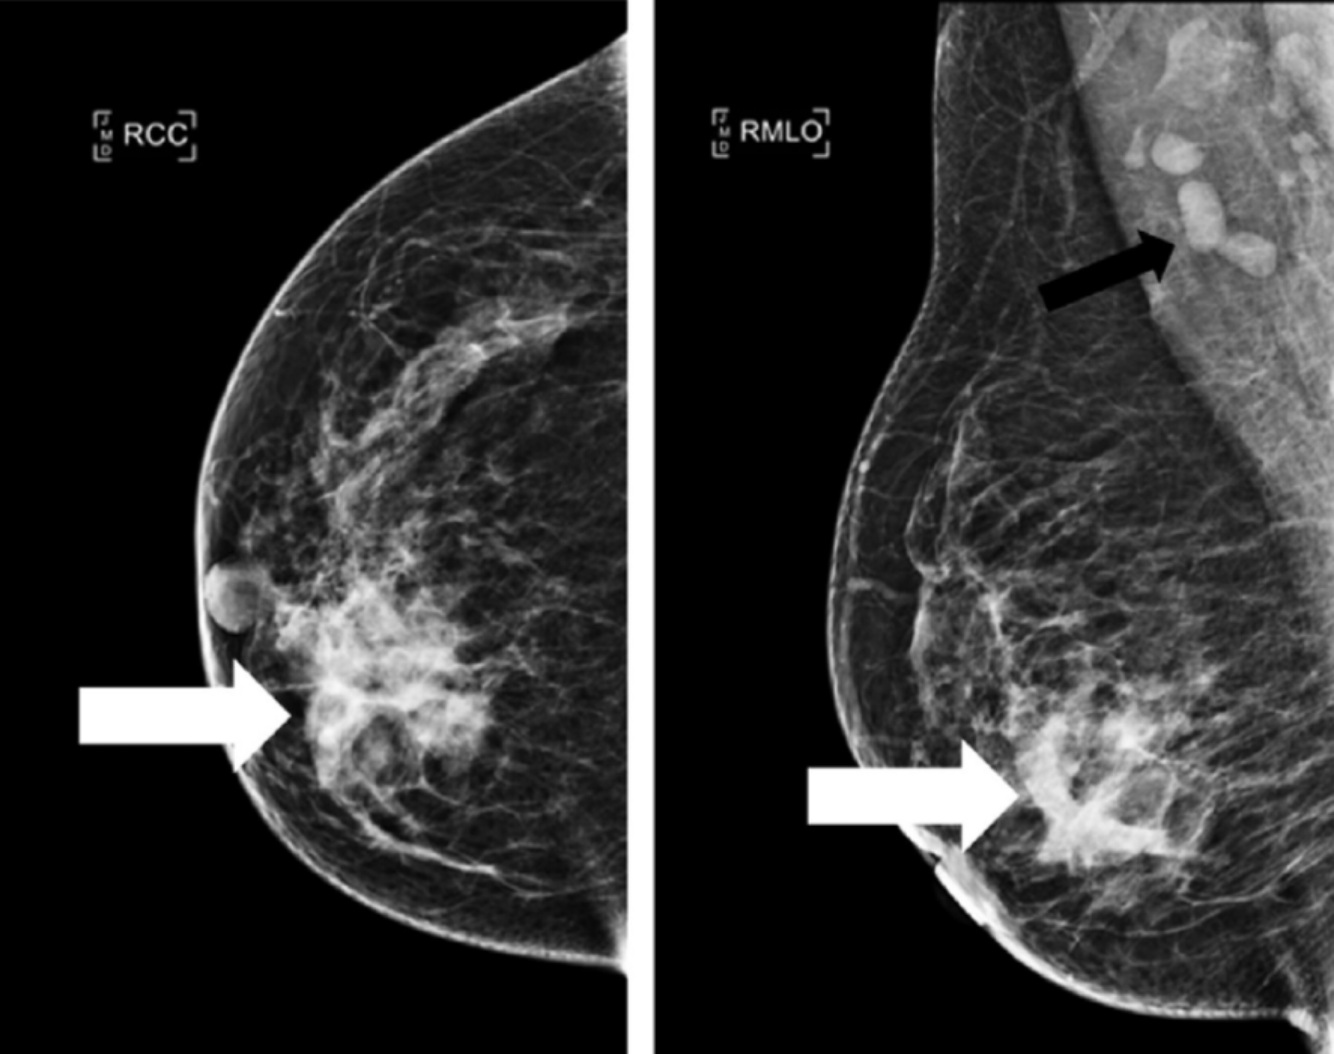

Q

Dx

A

Mastitis